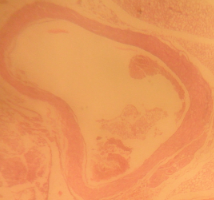

Morphological structure of aorta’s rats

Aorta’ slide was made every week for one month. Each group of the rats was killed, and the aorta’s rat was observed. From the morphological structure of aorta’s rat, atherosclerosis was scored as follows: on 4 point: 0, normal; 1, widening of elastic fibers with few foam cells; 2, fragmentation of elastic lamellae with numerous foam cells and fibrosis; 3, smooth muscle cells proliferation, medial lipid infiltration and fibrosis; 4, lipid-calcic plaque or ulcerated plaque [10].

Table 1: Distribution of aortic atherosclerosis scores at D90 in two groups of rat receiving atherogenic diet (n = 4)

| Lesions scores | A1 | A2 | A3 | A4 | B1 | B2 | B3 | B4 | C1 | C2 | C3 | C4 | D1 | D2 | D3 | D4 |

| 0 | - | - | 1 | 3 | - | - | - | 2 | - | - | - | - | 3 | 4 | 3 | 3 |

| 1 | 1 | 3 | 3 | 1 | 1 | 1 | 2 | 2 | 2 | - | - | - | - | - | 1 | 1 |

| 2 | 3 | 1 | - | - | 2 | 1 | 1 | - | - | 1 | 1 | 1 | - | - | - | - |

| 3 | - | - | - | - | 1 | 2 | 1 | - | 2 | 2 | 1 | 1 | - | - | - | - |

| 4 | - | - | - | - | - | - | - | - | 1 | 2 | 2 | - | - | - | - |

A1, A2, A3, A4 is morphological structure of aorta’s AND rats fed atherogenic diet for 2 mo and continuing with AND for 1 w, 2 w, 3 w and 4 w; B1, B2, B3, B4 is morphological structure of aorta’s atorvastatin rats fed atherogenic diet for 2 mo and continuing with atorvastatin for 1 w, 2 w, 3 w and 4 w; C1, C2, C3, C4 is morphological structure of aorta’s rats fed atherogenic diet for 9th week, 10th week, 11th week, 12th week; D1, D2, D3, D4 is morphological structure of aorta’s rats fed normal diet for 9th week, 10th week, 11th week, 12th week.

The rats (n=4) from each group were sacrificed every week to observe the morphological structure of the aortas. From the lesions, it showed that AND could help chance severity aortic atherosclerosis. The score varied from group A1 until group A4. The aorta morphology of group A1 showed that one aorta had a widening of elastic fibers with few foam cells (score 1) and three aortas had the proliferation of smooth muscle cells (score 3) (fig. 5 A1). AND administration for four weeks could repair aorta condition. Group A4’ aorta morphology showed that three aortas became normal (score 0) and one aorta still had a widening of the first interlamellar (score 1) (fig. 5 A4). Atorvastatin administration could also help changing the severity of aortic atherosclerosis. The score also varied from group B1 until group B4. The aorta morphology of group B1 showed that one aorta had a widening of elastic fibers with few foam cells (score 1), two aortas had fragmentation of elastic lamellae with numerous foam cells and fibrosis (score 2), and one aorta had the proliferation of smooth muscle cells (score 3) (fig. 5 B1). Atorvastatin administration for four weeks could improve aorta condition. Group B4’ aorta morphology showed that two aortas became normal (score 0) and two aortas still had a widening of the first interlamellar (score 1) (fig. 5 B4). Contrarily, the morphological structure of atherogenic rats was getting worse week by week.

Fig. 5: Morphological structure of aorta in albino Wistar male rats 40x. A1, A2, A3, A4 is morphological structure of aorta’s AND rats fed atherogenic diet for 2 mo and continuing with AND for 1 w, 2 w, 3 w and 4 w; B1, B2, B3, B4 is morphological structure of aorta’s atorvastatin rats fed atherogenic diet for 2 mo and continuing with atorvastatin for 1 w, 2 w, 3 w and 4 w; C1, C2, C3, C4 is morphological structure of aorta’s rats fed atherogenic diet for 9th week, 10th week, 11th week, 12th week; D1, D2, D3, D4 is morphological structure of aorta’s rats fed regular diet for 9th week, 10th week, 11th week, 12th week. Black circle (O) = score 1; green circle (O) = score 2; red circle (O) = score 3; blue circle (O) = score 4